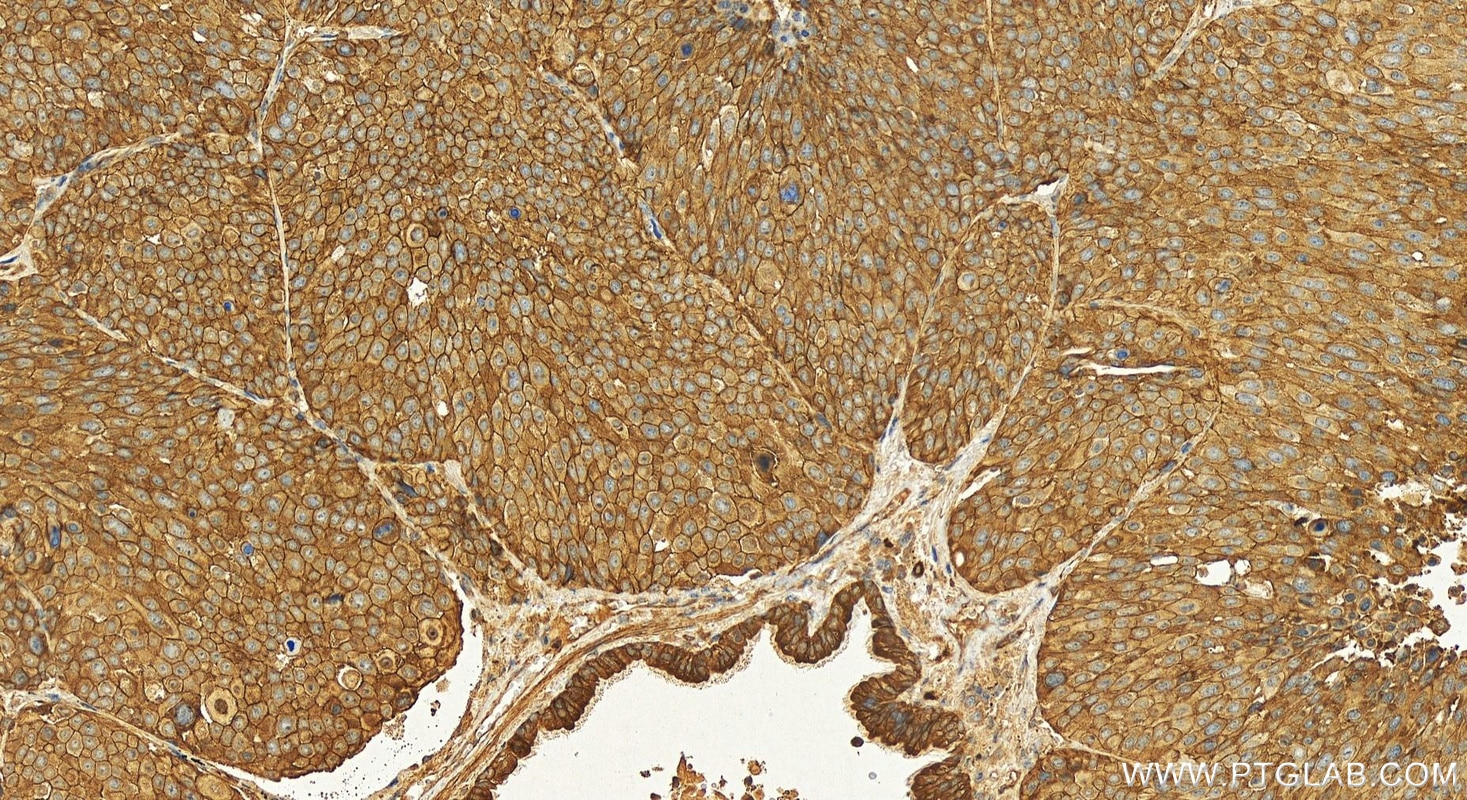

| Positive IHC detected in | human lung squamous cell carcinoma tissue Note: suggested antigen retrieval with TE buffer pH 9.0; (*) Alternatively, antigen retrieval may be performed with citrate buffer pH 6.0 |

31198-1-AP targets KIAA1522 in IHC, ELISA applications and shows reactivity with human samples.